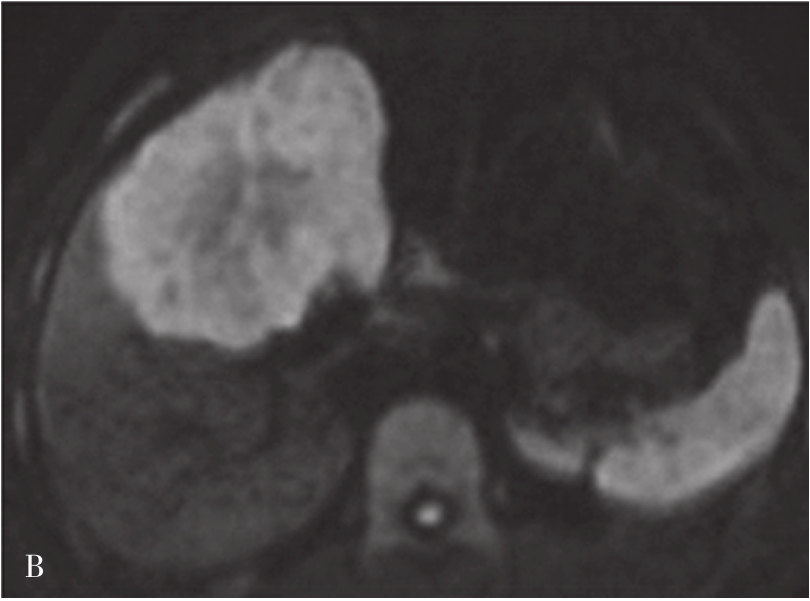

图5-21-42 HCC患者的MRI图像

A.T 2 WI脂肪抑制图像,可见肝右前叶内较大略高信号为主的病灶,内有点状更高信号影及中央低信号区,边界较清楚;B.600s/mm 2 时DWI图像,可见病灶为略高信号为主,中央略低信号;C.脂肪抑制图像,可见病灶为低信号影,边界较清楚,其内有一高信号影(箭头),为出血信号;D.增强扫描动脉期图像,可见病灶内轻微强化;E.可见门脉期图像病灶不均匀强化;F.可见延迟期图像病灶大部强化,中央无强化,假包膜清楚

HCC最常见的MRI表现为T 1 WI呈略低信号,T 2 WI呈略高信号,DWI呈高信号(图5-21-42)。有文献报道T 1 WI呈等信号者,多为分化较好的早期HCC,而脂肪变、出血、坏死、细胞内糖原沉积或铜沉积可导致病灶在T 1 WI上呈高信号,此外,在肝血色病基础上发生的HCC,由于肝实质在各脉冲序列图像上信号均很低,病灶一般都呈相对高信号。肿瘤假包膜可见于40%~70%的结节型和巨块型HCC。Gd-DTPA增强较为特征性的强化形式是对比剂“快进快出”,其原理为这些病灶70%的血供来自肝动脉,延迟相上出现宽0.5~3mm的包膜强化也颇具特征。采用特异性肝细胞摄取的对比剂,比如钆塞酸二钠(Gd-EOB-DTPA,普美显)不仅有其他钆类对比剂同样的动态增强外,在静脉注射10~30min内约有50%被正常肝细胞摄取,而不含正常肝细胞的HCC则很少或基本不摄取,而在肝特异性期呈低信号。有助于小HCC与肝硬化再生结节和其他良性病变的鉴别。大多数HCC在肝特异性期呈现相对低信号,但约10%的分化程度较好的HCC亦可呈等或高信号。